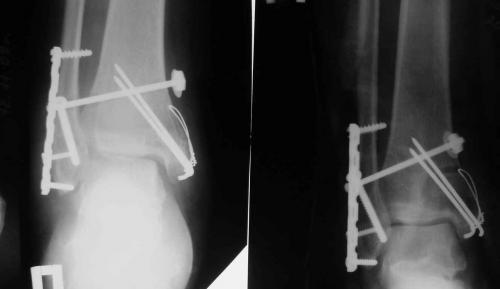

При смещении костных отломков для их более надежной фиксации используется остеосинтез.

- Открытая репозиция с фиксацией погружными конструкциями. Таким путем лечат все открытые и часть закрытых переломов. В некоторых случаях после операции сустав дополнительно фиксируют гипсом.

- Скелетное вытяжение и чрескостный компрессионный остеосинтез. Используются для лечения сложных и застарелых переломов в области голеностопного сустава. Проводится с помощью специальных аппаратов внешней фиксации.